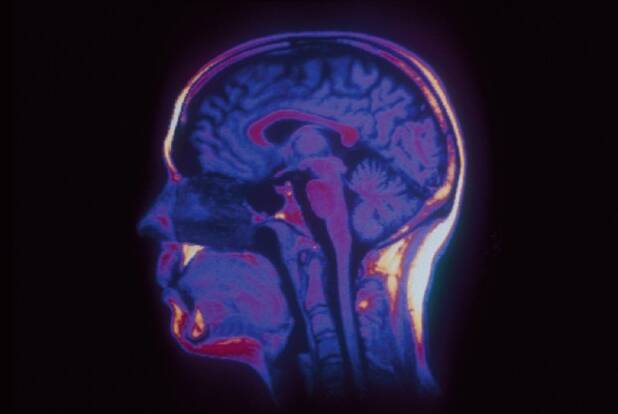

Il est très difficile de savoir quelle est la part génétique et héréditaire dans l’intelligence. Le débat sur les déterminants du QI, le coefficient intellectuel, est ancien et extrêmement complexe.

Il reste que les Chinois viennent d’ouvrir un programme géant de sélection de cerveaux surdoués, c’est-à-dire avec un QI égal ou supérieur à 160. L’institut Beijing Genomics Institute, le plus centre de séquençage de l’ADN au monde, veut comparer ce qui diffère dans le cerveau des surdoués du cerveau des personnes au QI standard.

Cela ne va pas être une mince affaire, mais la science progresse si vite qu’il ne faut pas parier sur l’échec des Chinois. Au contraire, malgré la complexité d’un cerveau humain doté de quelque 100 milliards de neurones chacun doté de milliers de connections changeantes, il y a fort à parier que les Chinois (et d’autres labos dans le monde) arrivent un jour ou l’autre à une compréhension suffisante du génome humain pour agir dessus. De là à en faire une arme dans la bataille économique, il y a un (grand) pas que certains envisagent déjà.